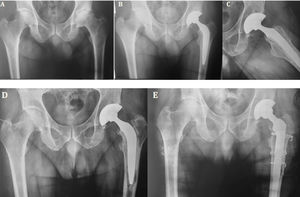

Female patient aged 48years. (A) Preoperative AP projection: left hip osteoarthritis is observed. (B, C) Total hybrid replacement, immediate postoperative control. (D) Control at 14years: evolution with loosening of the femoral component. (E) Revision to distal fixation stem with extended femoral osteotomy.

Group A (cemented) presented the highest percentage (73.3%) of cups with signs of demarcation and group B (hybrid) presented the highest rate of stems with signs of demarcation (78.2%), representing a statistically significant difference when comparing the three groups (p<.001). Cementation quality analysis raised no significant differences between groups A and B (p=.17) (Table 4; Fig. 2).